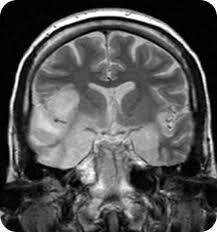

La neuropsicología infantil estudia las relaciones entre el cerebro y la conducta/cognición dentro del contexto dinámico de un cerebro en desarrollo (Anderson y cols., 2001).

Anderson y colaboradores (2001) han propuesto tres dimensiones del conocimiento que deben incluirse en el análisis de los procesos cognitivos/comportamentales y sus relaciones con el sistema nervioso, estudiados por la neuropsicología infantil: la dimensión neurológica, la dimensión cognitiva y nalmente, la dimensión psicosocial.

El objetivo general de la neuropsicología es el estudio de la organización cerebral de la ac-tividad cognitiva-conductual, así como el análisis de sus alteraciones en caso de patología cerebral (Ardila y Rosselli, 2007).